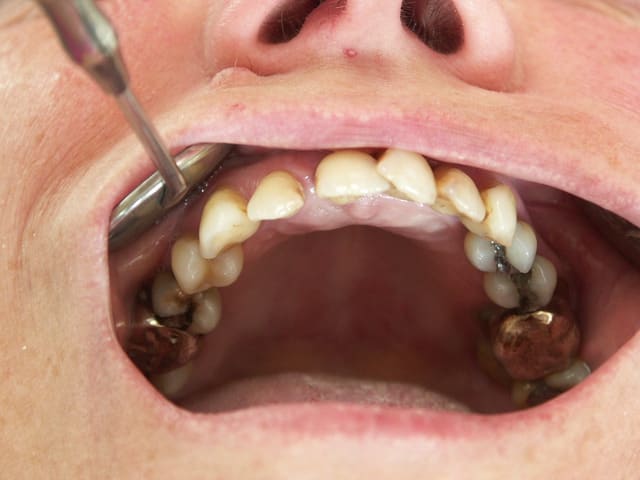

cas 1 cool mais ROG à la truelle!

cas 2 l'ex° de la 13 sans casse n'est pas gagné

et es tu certain pour l'implant 8? mettre un 14mm dans une cloison de sinus je ne suis pas pxav

Celui la est très moyen au niveau osseux

22 implants au total et pas une seule vis!

Pluton 2 max stab, tu vois cela m'arrive aussi d'en mettre!

Voila c'est fait!

Je laisse Posit mettre les photos des cas. Son bébé a encore franchi un cap

Ce n'est pas réalisable avec toutes les marques d'implants

0 vis et 0..... (A vous de deviner) , pour moi c'est le summum. Bien sur cela n'engage que moi